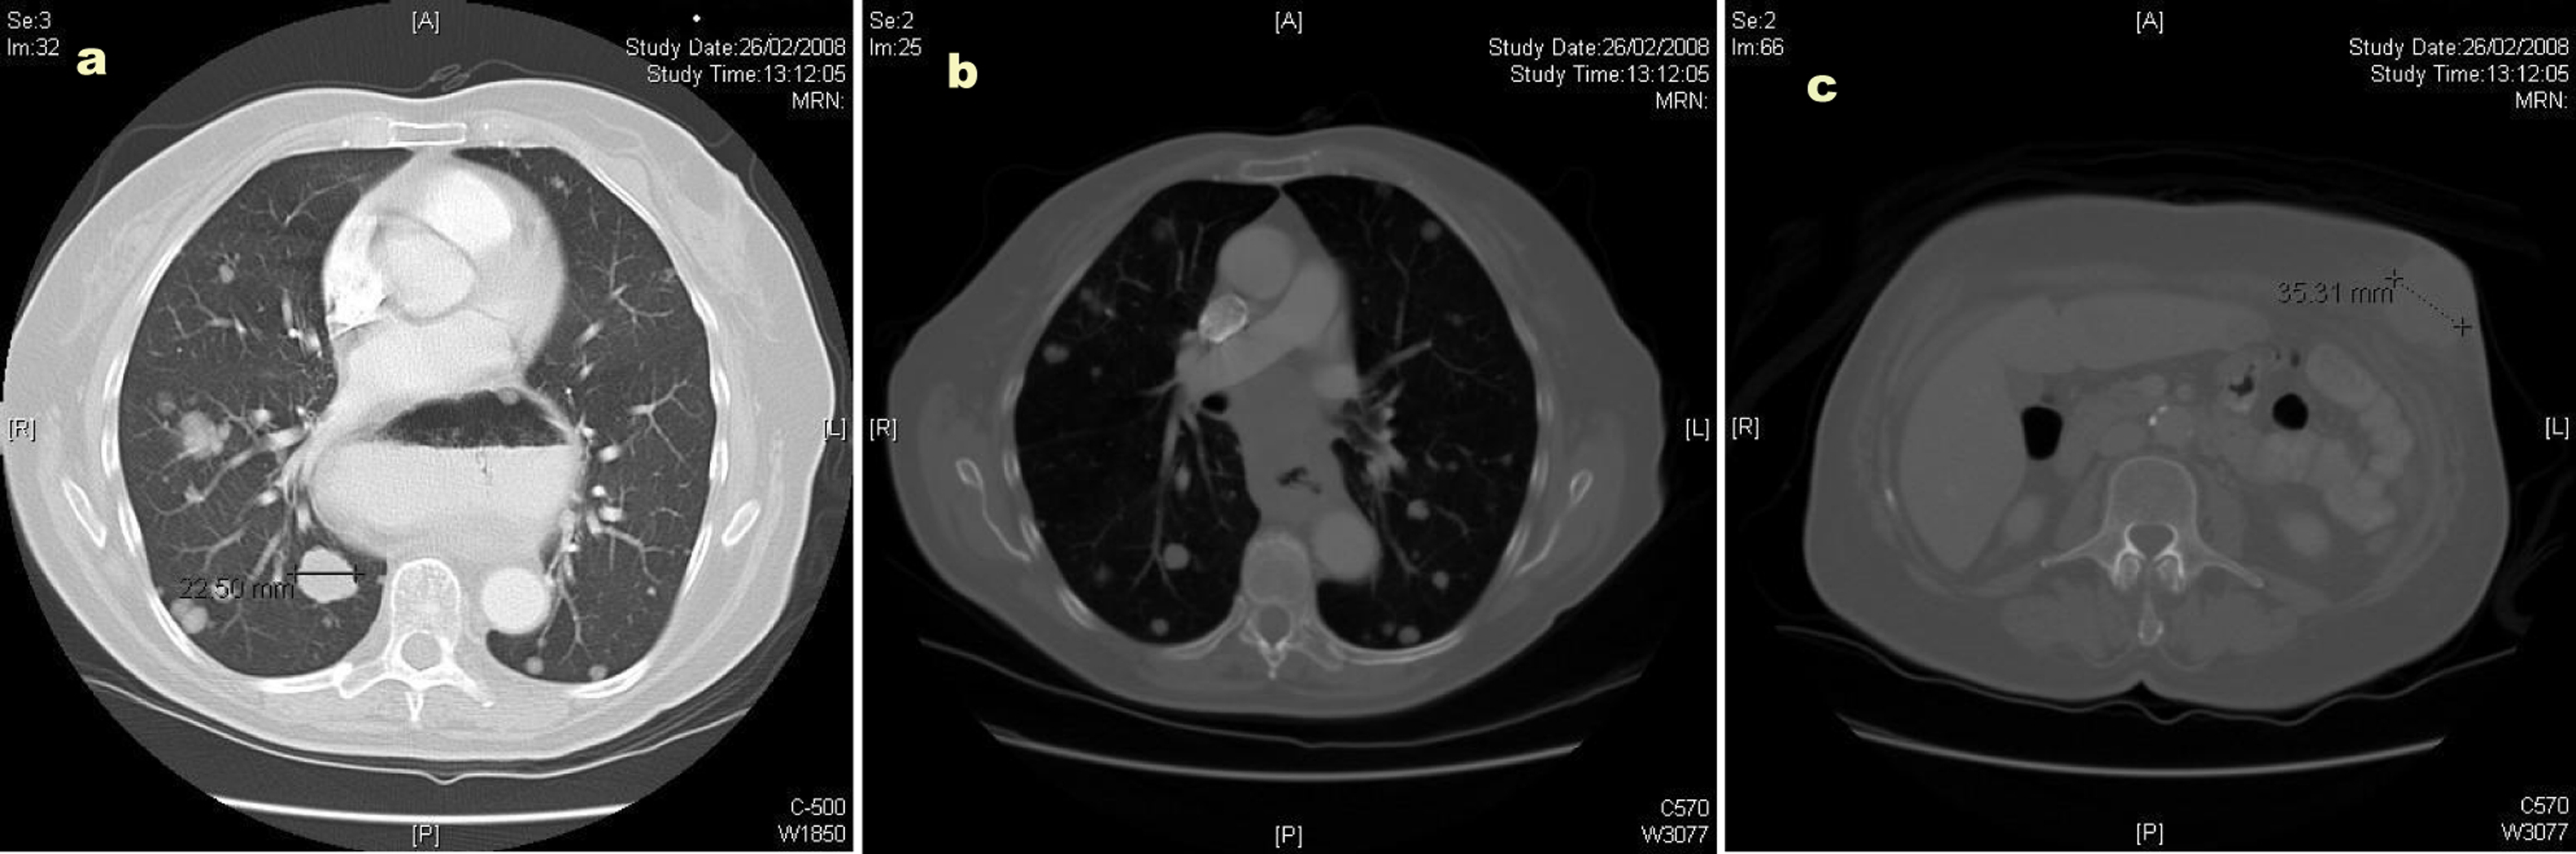

The CT scan showed widespread metastatic disease. Beginning cranially, within the lungs there were multiple rounded nodules of varying size, the largest measuring 23 mm, consistent with metastases. In the right superior mediastinum there was an enlarged node measuring over 2 cm. This node was separated from the right lobe of the thyroid by the jugular vein but posteriorly shown to be inseparable from the upper thoracic esophagus. The distal esophagus and gastro-esophageal junction was noted to be abnormally circumferentially thickened and irregular; however, there was no proximal dilatation of the esophagus. There were further metastatic deposits in the liver, kidneys and omentum. A number of subcutaneous and intramuscular lesions were identified throughout the thorax and abdomen, but no lytic bone lesions. The original left abdominal mass was identified as originating from the anterior abdominal wall and extending into the subcutaneous tissue: Figures 2a, b and c illustrate CT images of multiple lung metastases (the largest measuring 22.50 mm), of the circumferential esophageal wall thickening consistent with the primary tumour, and of the anterior abdominal wall lesion, respectively.

![]() Click for large image | Figure 2. (a) Computed tomography (CT) image illustrating multiple lung metastases; (b) Computed tomography image illustrating circumferential esophageal wall thickening; (c) Computed tomography image illustrating the anterior abdominal wall lesion. |